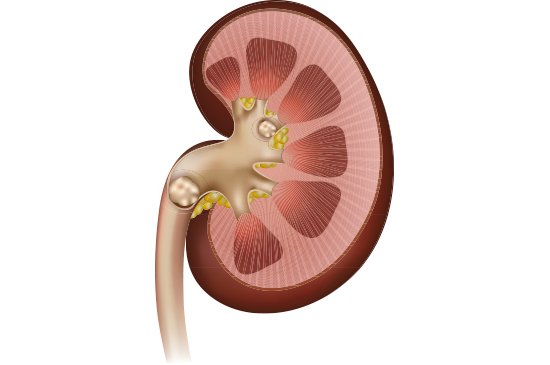

Cálculo Renal: Como eles se formam?

Os cálculos renais se formam devido a agregação de cristais de algumas substâncias excretadas na urina, como por exemplo o oxalato, cálcio, fosfato e o ácido úrico.